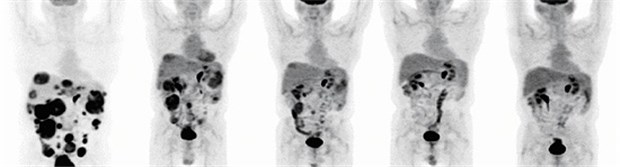

PET-Aufnahme bei einem GIST-Patienten.

© Siemens AG Medical Solutions

Magen-Karzinom

Neue Hoffnung bei Stromatumoren